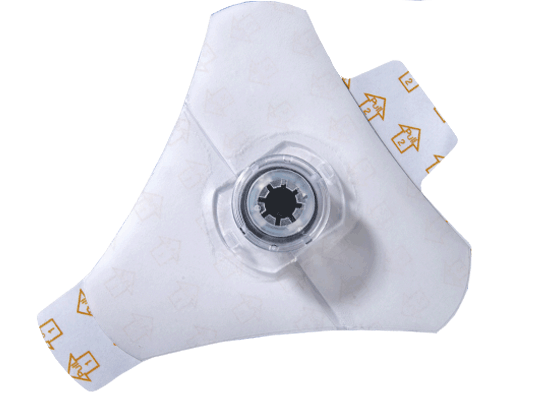

EZ-Stabilizer® Dressing |